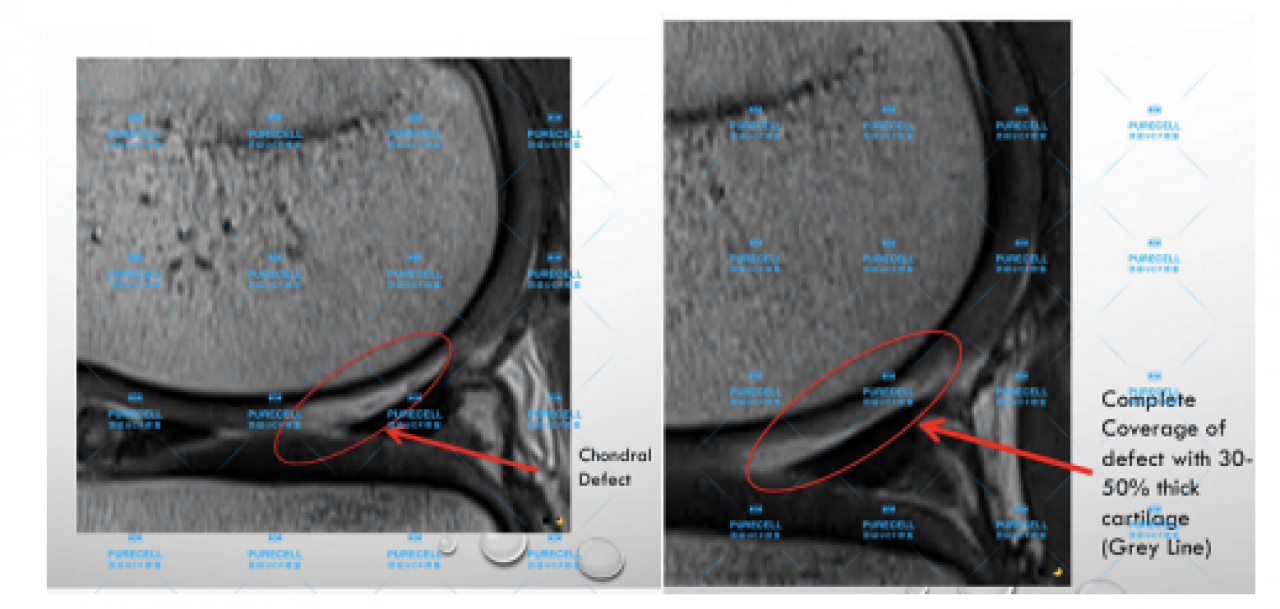

PURECELL首席科學家以及運動醫療專家已經驗證了UCF對膝關節修復的有效性,下圖是UCF軟骨及半月板修復前後影像對比。

PURECELL金牌資質醫生Dr. Ian Chinse說,UCF膝關節修復的主要原理是通過UCF成分,改善膝關節內環境,有效激活幹細胞靶向修復膝關節組織,修復韌帶損傷、半月板損傷,修復軟骨及髕骨等組織,能有效較少軟骨受損、骨刺等所帶來的疼痛,並且有效避免了軟骨、半月板等膝關節組織的持續磨損和惡化,從根源上改善膝關節疼痛等問題給生活帶來的困擾。